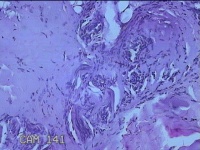

性别

男

年龄

41岁

临床诊断

皮脂腺痣

一般病史

双下肢红斑痒一年余。

标本名称

双下肢肿物

大体所见

灰白暗红色肿物0.8x07x0.3cm一个,表面糜烂。

图1